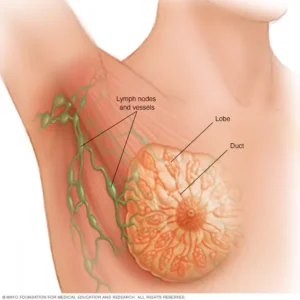

سرطان الثدي نوع من السرطان يبدأ على هيئة نمو للخلايا في نسيج الثدي. ويأتي سرطان الثدي بعد سرطان الجلد من حيث كونه أكثر أنواع السرطان

جراحات أورام الثدي مش معناها إزالة الثدي بشكل كامل! في المراحل الأولى من أورام الثدي بنلجأ لتقنية الاستئصال التحفيظ او استئصال تجميلي للثدي اللي بيتيح

إعادة بناء الثدي باستخدام الغرسات هي جراحة تهدف إلى استعادة شكل الثدي باستخدام غرسة ثدي. وتُجرى هذه الجراحة في الأغلب بعد جراحة استئصال الثدي التي

تلجأ كثير من النساء إلى جراحة الثدي التجميلية، رغبةً في الشعور بالمزيد من الثقة، تعال معنا لنتعرف أكثر على جراحة الثدي التجميلية في السطور الآتية:جراحة